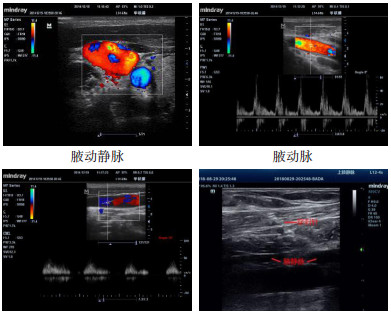

(1)Magney穿刺法按Magney提出的体表定位法[4]选取定位点。先取两条线:一条是胸骨角中心与肩胛骨喙突的连线,取其中外1/3交点为进针点;另一条是胸锁关节与肩锁关节的连线,取其中内1/3交点为目标点。目标点为腋静脉与锁骨下静脉移行处,即腋静脉上段。穿刺针与胸壁呈30°~45°负压缓慢进针,靶点处刺入静脉,进针深度参考锁骨和第一肋骨间隙。见图 1[4]。(2)超声引导穿刺法:在锁骨中内侧部分下方,局部加压或应用脉冲多普勒波形确认动静脉。静脉容易压扁,波形平坦,动脉搏动感强,波形高尖。探头长轴放置于静脉上,穿刺针与胸壁呈30-45°负压缓慢进针,通过超声显示器明确针道进入静脉,穿刺针内见暗红色血液。见图 2

图 2 超声引导下腋动静脉及穿刺图示 Fig 2 Ultrasound-guided axillary arteriovenous and puncture graphics